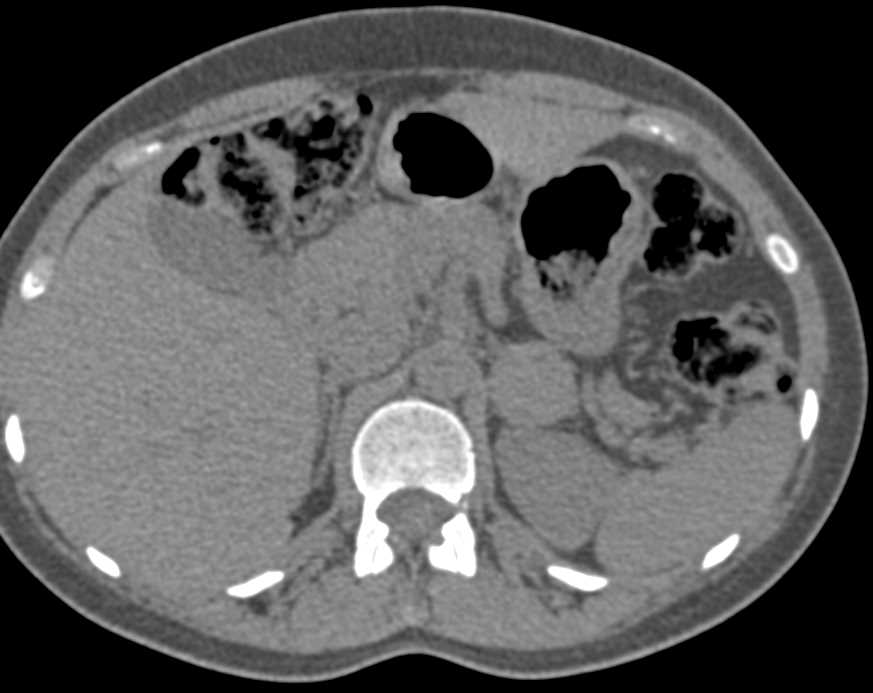

Superior Mesenteric Artery (SMA) Syndrome Based Solely on Patient Symptoms